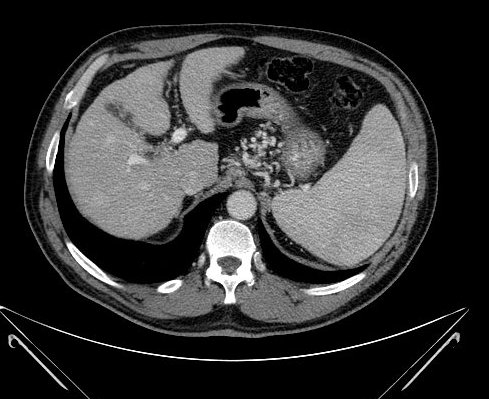

Nowadays, CT is a basically important method amongst the modern diagnostic imaging services. (Figure 4) By the application of the multidetector CTs a chance is given to perform multiphase (without contrast, arterial, portal and late phase) CT scans, which provide important additional information because of the different hemodynamics of certain intrahepatic nodules. Multiplanar (sagittal, coronal, oblique) and 3D reconstructions can be adopted from the axial plane CT slices. Due to CT angiographic techniques, excellent spatial resolutional 3D reconstructional images can be performed both on the arterial (hepatic artery) and the venous sides (portal vein, hepatic veins, collateral veins in case of portal hypertension, CT control of transjugular portosystemic shunts)..

Figure 4. Liver, contrast enhanced CT, venous phase